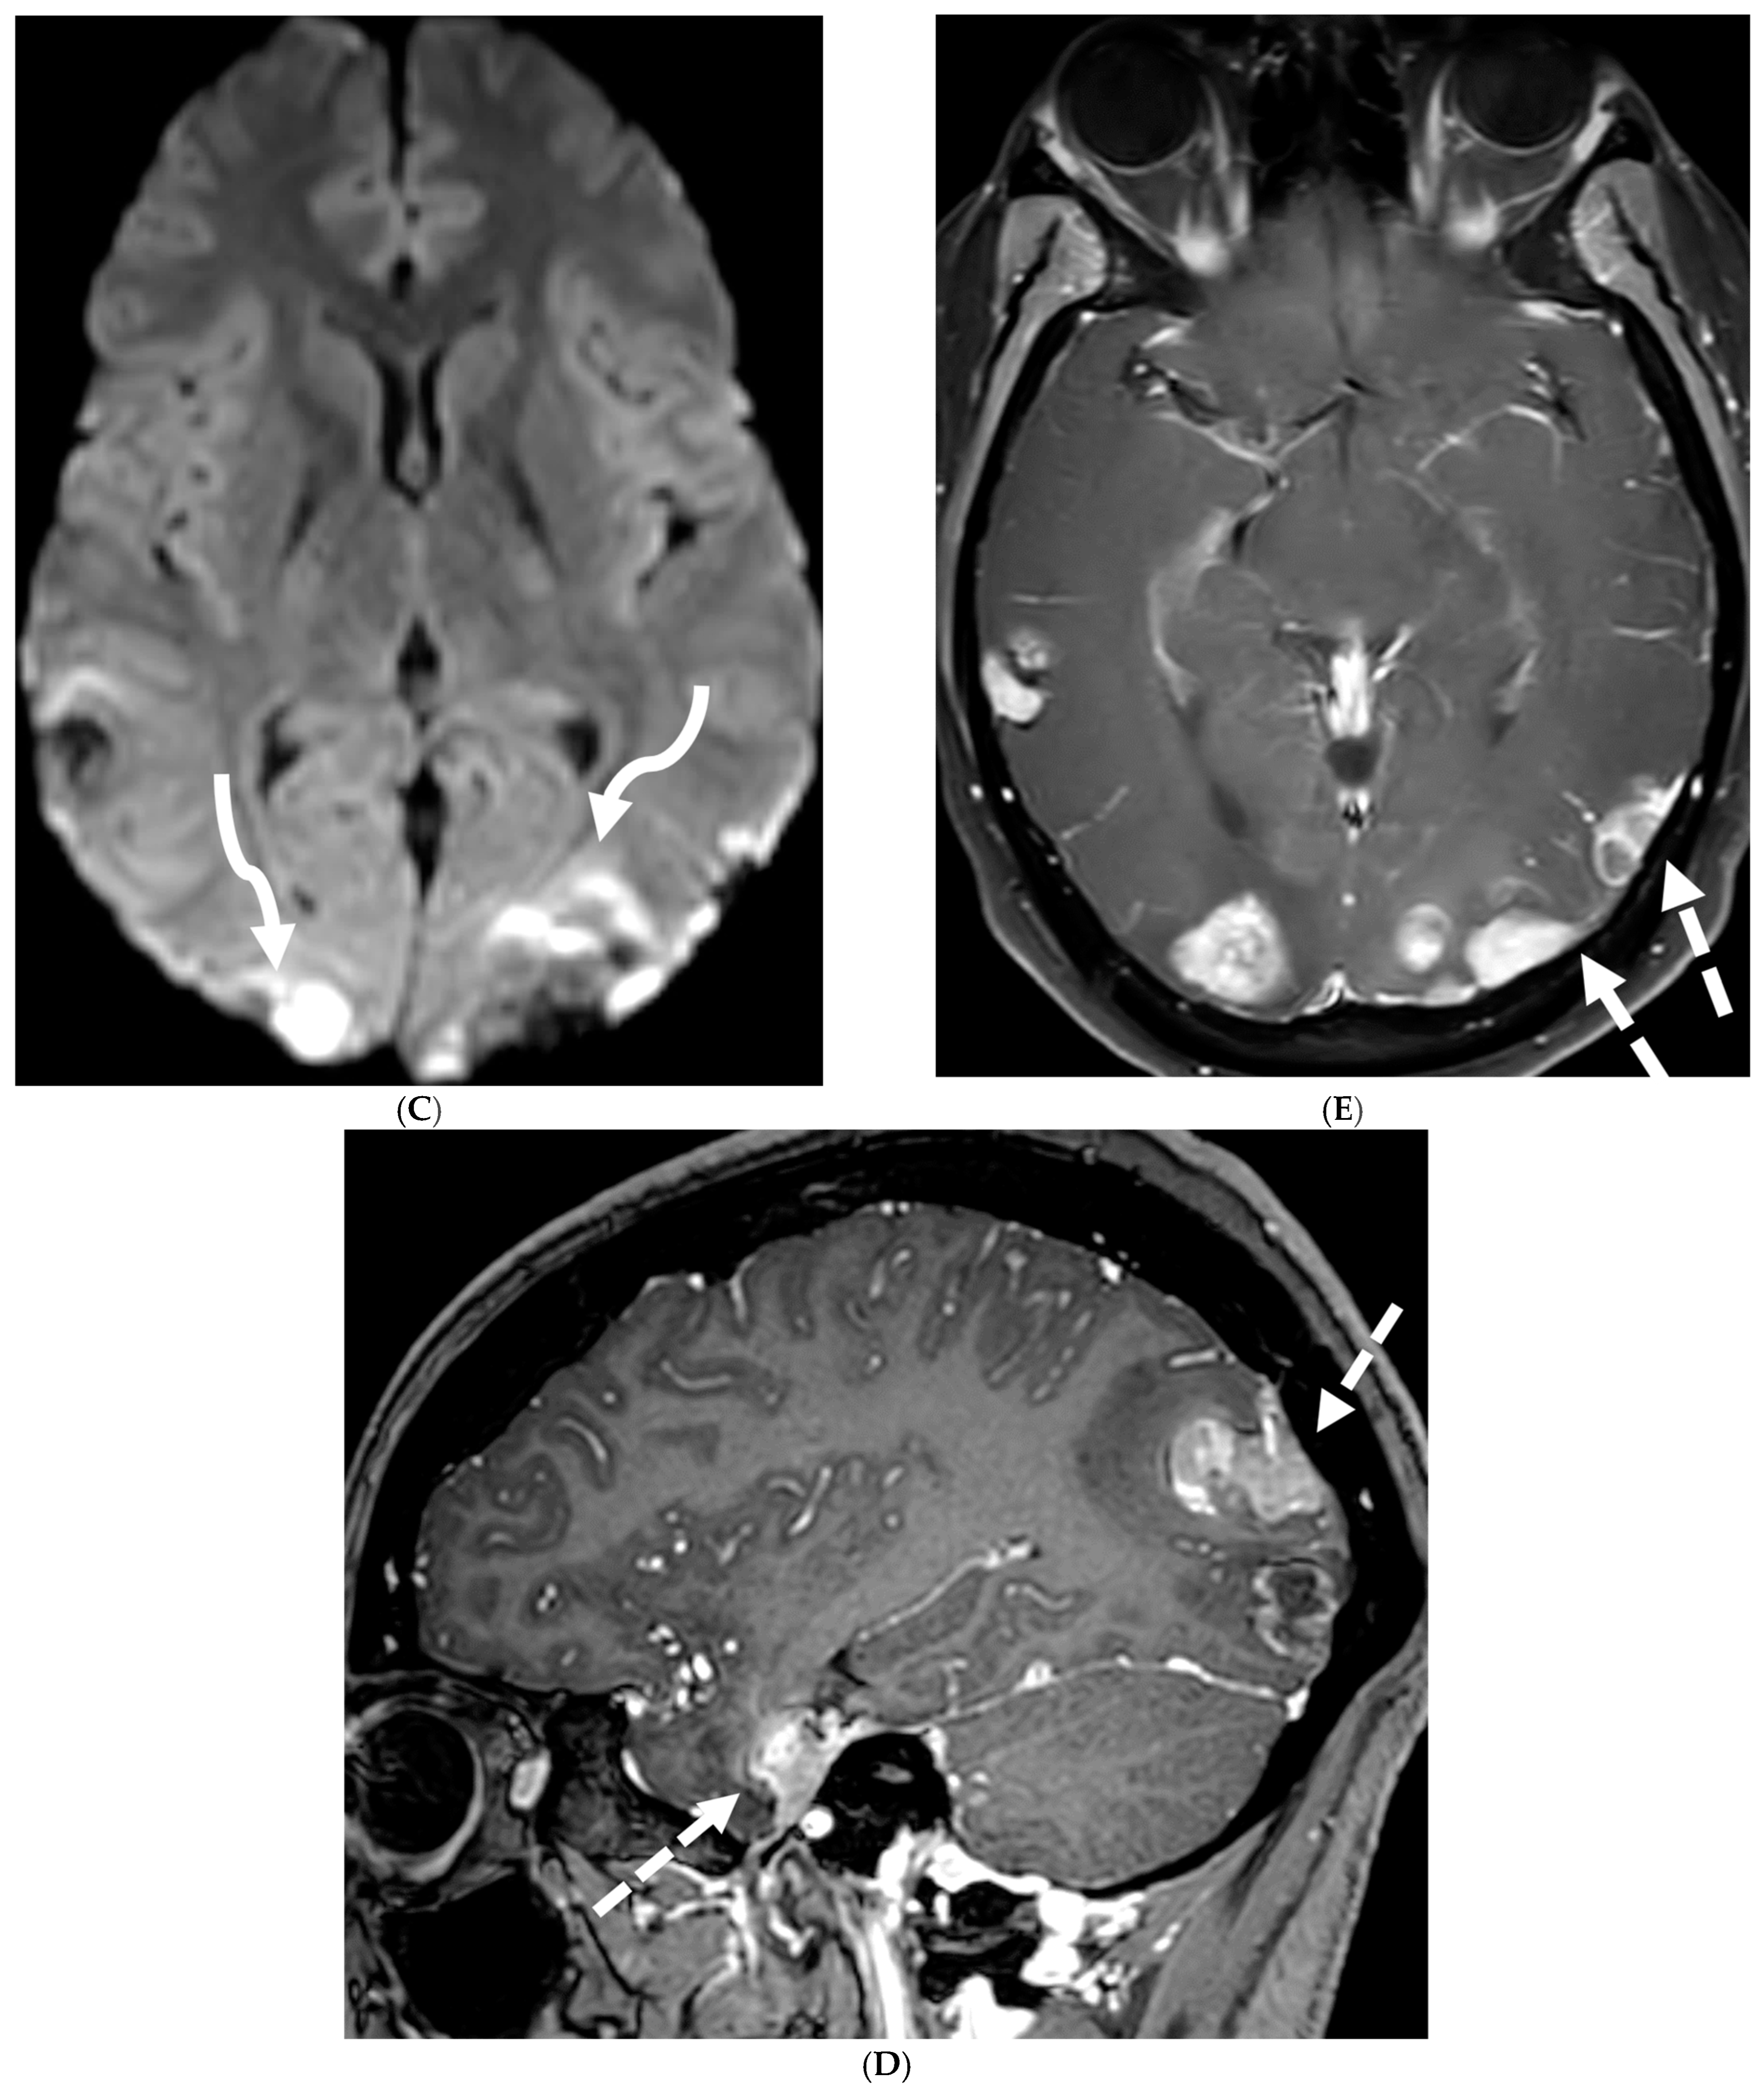

The typical MRI presentation of SMM involves serpentine, nodular, or plaque-like enhancement in sulcal spaces, basal cisterns and along the cauda equina nerve roots [87,88]. Notably, SMM enhancement on post contrast [PC]-T1 images is superior to the PC-FLAIR in contrast to that seen in infectious meningitis [84]. However, in case of a non-enhancing primary tumor, FLAIR and DWI are important sequences to look for SMM. Hydrocephalus and subependymal deposits are other common features found in kids with SMM (Figure 15, Figure 16 and Figure 17). Positive cytology on CSF analysis, especially with leukemia, is important [89].

Figure 15.

Axial DWI (A), axial ADC (B), axial T1 FS post contrast (C) and Fluorodeoxyglucose Positron Emission Tomography (FDG–PET) scan (D): 13-year-old male with bilateral leg pains, headache, fever and weight loss: Blood tests and CT scan were concerning for Burkitt’s lymphoma. There is heterogeneous calvarial bone marrow signal with restricted diffusion (arrows) and patchy enhancement (curved arrows). Diffuse thickening and enhancement of pachymeninges in the supratentorial compartment is noted (dashed arrows). Findings are most consistent with lymphomatous involvement. Multifocal diffuse/heterogeneous pattern of FDG uptake within the axial and appendicular skeleton and the calvarium (open arrows). Intense FDG avid uptake is seen in the presacral mass (star).

Figure 16.

16-year-old female with 4 months history of globus sensation and recent botox injection of lower esophageal junction. Headache and vomiting for past week: Esophagogram (A), Axial T2 orbits (B), axial FLAIR (C) and post contrast T1 (D,E): Narrowing of the Gastroesophageal (GE) junction with beaked configuration and mild distention of the lower esophagus likely from early achalasia (black arrow). There is bilateral papilledema indicating raised ICP (dashed arrows) and sulcal hyperintensity (curved black arrows). Diffuse LME in the supra-and-infratentorial regions and along optic sheaths raising the concern for leptomeningeal carcinomatosis (white arrows). Pathology: Gastric adenocarcinoma metastasis.

Figure 17.

Axial T2 FS (A), axial Susceptibility weighted imaging (SWI) (B), axial DWI (C), post contrast sagittal and axial T1 post contrast (D,E): 19-year-old female with history of stage IV neuroblastoma, left paraspinal primary ganglioneuroblastoma, treated with chemotherapy, radiation and bone marrow transplant presents with headache. There are extensive hemorrhagic leptomeningeal masses, both supra and infratentorial region (arrows). The lesions also demonstrate restricted diffusion which could be secondary to internal hemorrhage or high cellularity of the tumor(curved arrows). The larger masses invade the cortex of both cerebral hemispheres, with surrounding vasogenic edema (black arrow). Avid enhancement of the lesions is seen along with overlying dura (dashed arrows). Features are in keeping with extensive leptomeningeal metastatic neuroblastoma.